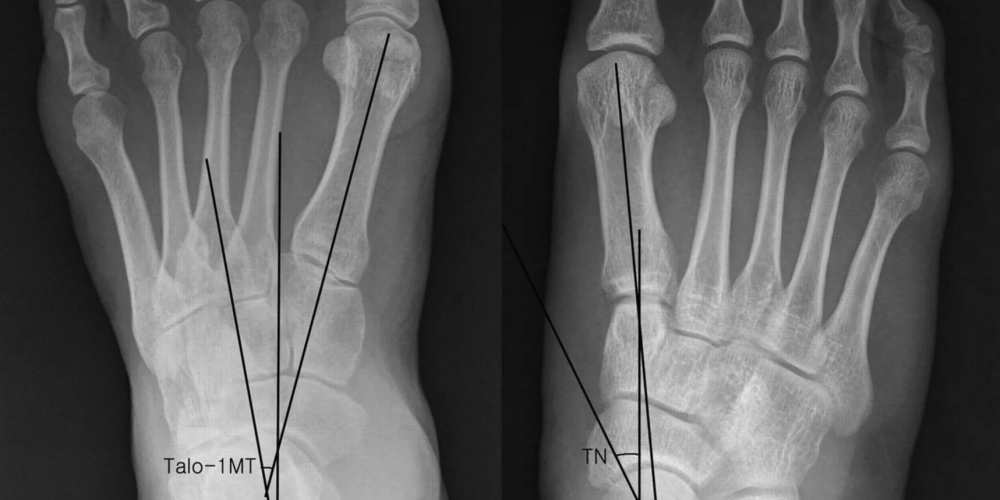

Диагностика вальгусной деформации

Составляющие диагностики вальгусной деформации стоп:

- инструментальные исследования – рентгенография стоп, плантография, подометрия;